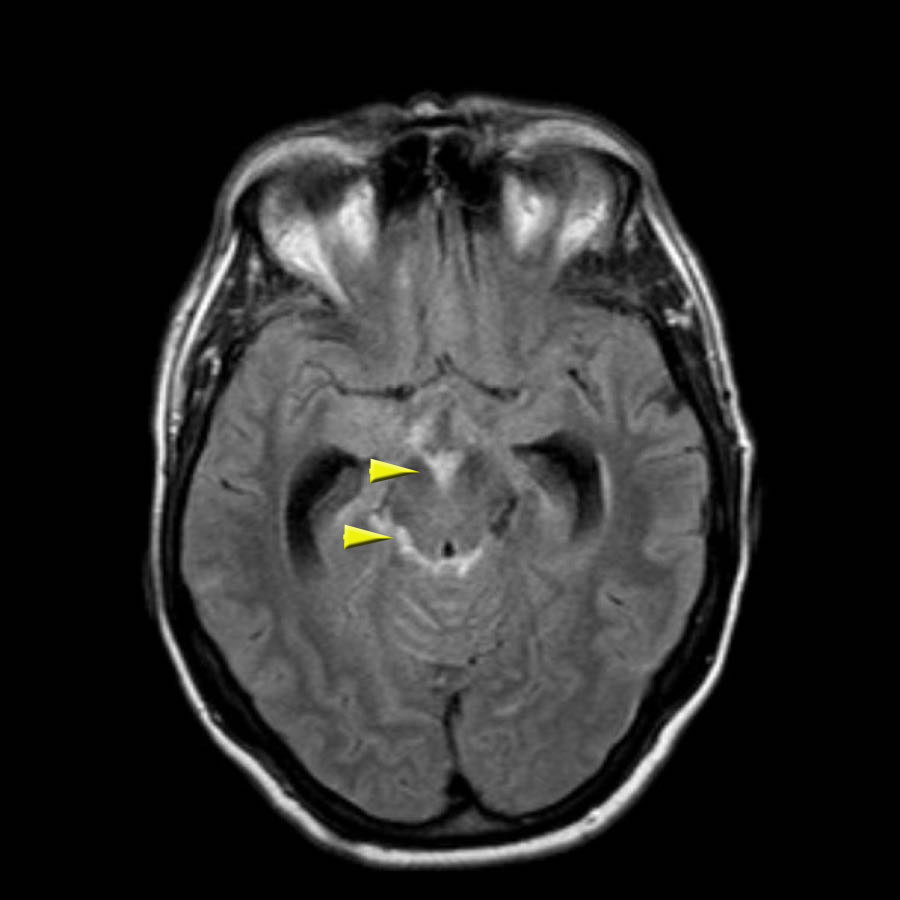

Bệnh nhân CAA này có xuất huyết vi thể, nhiễm sắt bề mặt và nhiều ổ nhồi máu.

Lưu ý ổ xuất huyết ở cầu não (mũi tên vàng).

Có hình ảnh nhiễm sắt bề mặt ở vùng chẩm trái.

Chuỗi xung DWI cho thấy ổ nhồi máu ở thùy chẩm trái và thùy trán phải (kèm theo một số xảo ảnh).